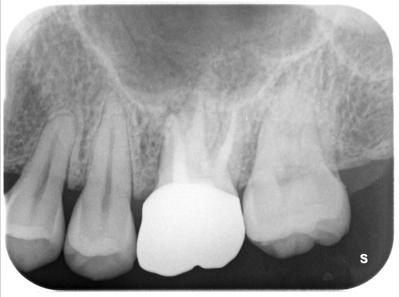

フィステル(サイナストラクト)ができたとのことで来院。

◯で囲った部分が何やら怪しい。

上顎洞が押し上げられるように膿が溜まっている。